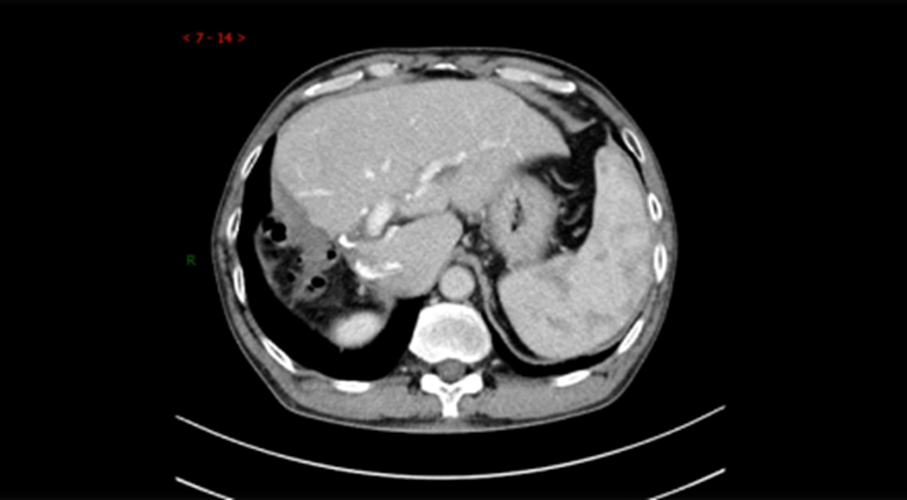

➣ 2019年4月23日,腹部增强CT:右肝巨块型肿块,大小约16*15*10cm,伴周围子灶形成;右肝静脉、门静脉右后支受侵;肿块体积 1236.63㎝³,左肝体积 863.97㎝³。

➣ 病灶及受累血管局限在右半肝;Child-Pugh A级;剩余肝体积 / 标准肝体积 > 40%;ICG 15分钟滞留率=25%。因此,不可手术切除。

疗效评价1

mRECIST评价标准:PR

➣ 目标病灶(动脉期增强显影)的直径总和缩小>30%

肿瘤体积明显缩小:749.25⁄1236.63 cm³ ≈60%

➣ 病灶及受累血管仍局限在右半肝,且病灶缩小;安全性:Child-Pugh A级;剩余肝体积 / 标准肝体积 > 40%;ICG 15分钟滞留率=6.4%,手术切除可行。